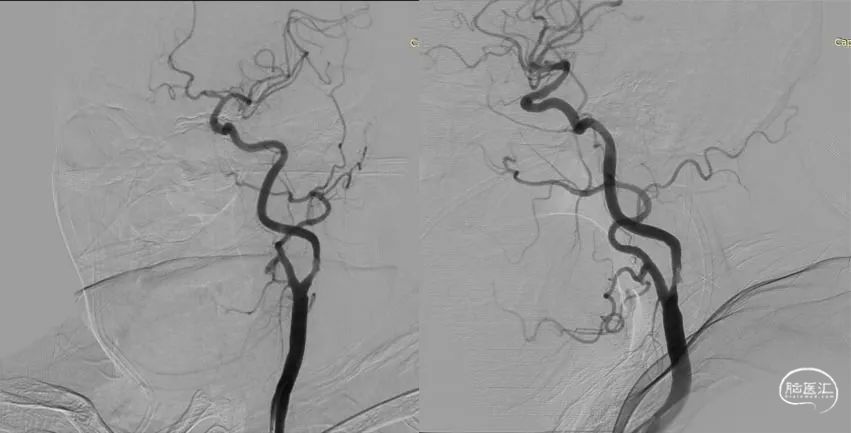

在脑梗死发病的第5天(NIHSS 3分),患者进行了全脑血管造影,提示左侧颈内动脉起始部中度狭窄伴血栓形成,同侧颈内动脉远段、大脑中动脉显影良好(图1)。

图1:左侧颈动脉造影